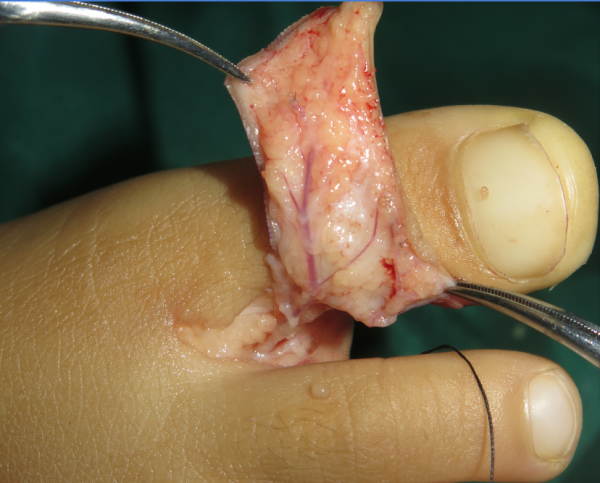

昨天急诊小皮瓣

QQ截图20160919232401.png QQ截图20160919232425.png QQ截图20160919232442.png QQ截图20160919232457.png